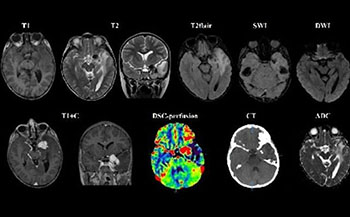

МРТ исследования головного мозга и DSC-перфузия. В области левого кавернозного синуса экстрааксиальное образование, с широким прилежанием к ТМО, окруженное перифокальным отеком и масс-эффектом на медиальные отделы височной доли левого полушария головного мозга. При анализе Т2 и Т2flair изображений, визуализируется особенный симптом «Инь-Ян», характеризующийся наличием двух компонентов у опухоли, один из которых гипоинтенсивный (гипоклеточная часть, представленная коллагеновой стромой), а другой гиперинтенсивный (гиперклеточная часть) по отношению к мозговой паренхиме. Кроме того данное образование демонстрирует гомогенное, относительно однородное накопление парамагнетика на постконтрастных изображениях, а так же наличие диспластически расширенных сосудов опухоли на SWI последовательностях, что отчетливо подтверждается высоким кровоснабжением данной опухоли на перфузионных картах с высокими значениями rCBV. Бесконтрастная Кт – демонстрирует неоднородную опухоль с наличием в структуре кальцинатов.⠀В настоящее время нет никаких патогномоничных признаков в диагностике данной опухоли, но симптом «Инь-ян» и выраженное гетерогенное контрастирование могут внести определенный вклад в диагностике данного образования.⠀Солитарная фиброзная опухоль (послеоперационный микропрепарат), окраска гематоксилином и эозином, увеличение х10. а – гипоклеточная зона образования, представленная прослойками коллагена (черные стрелки). б – гиперклеточная зона (красные стрелки), а так же наличие тонкостенных диспластично расширенных ветвящихся сосудов по типу «рогов оленя» ("staghorn" sign)